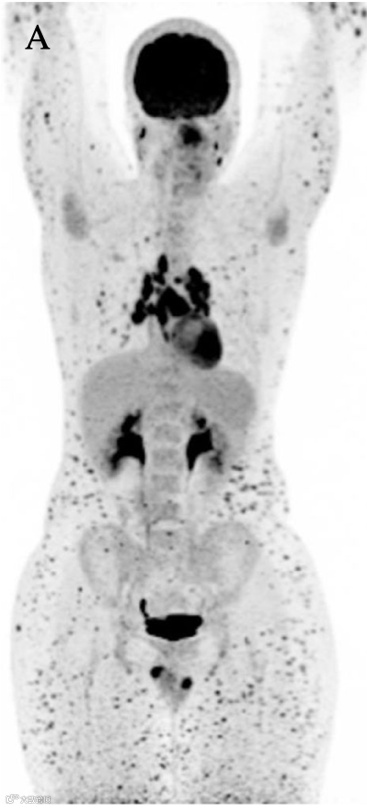

在揭晓谜底之前,我们先来做一个“盲测”。下面有两张经典PET/CT全身MIP 图,请凭借你的直觉,谁是老虎?谁是雪豹?

图A 是“雪豹征” (Snow Leopard Sign)

雪豹追踪

和老虎的条纹不同,雪豹的特点是全身布满了“圆点状、结节状” (Spotty/Nodular) 的高代谢灶。MIP 图上看,就像是一只潜伏在雪地里的豹子身上的斑点。

“豹纹”是皮下的结节。这种征象的核心定位在皮下组织(Subcutaneous tissue)和皮肤。它不是深层的肌肉,而是浅层的脂肪和软组织。

头号嫌疑人:依然是结节病!你没看错。这次是皮下/皮肤结节病(Cutaneous/Subcutaneous Sarcoidosis)。结节病就是这么狡猾,它既能变成老虎(侵犯肌肉),也能变成雪豹(侵犯皮下)。

危险嫌疑人:皮下脂膜炎样T 细胞淋巴瘤(SPTCL)。这点必须警惕!文献Molecular Imaging and Radionuclide Therapy (2023)专门报道了SPTCL 也会表现为酷似“雪豹”的征象。